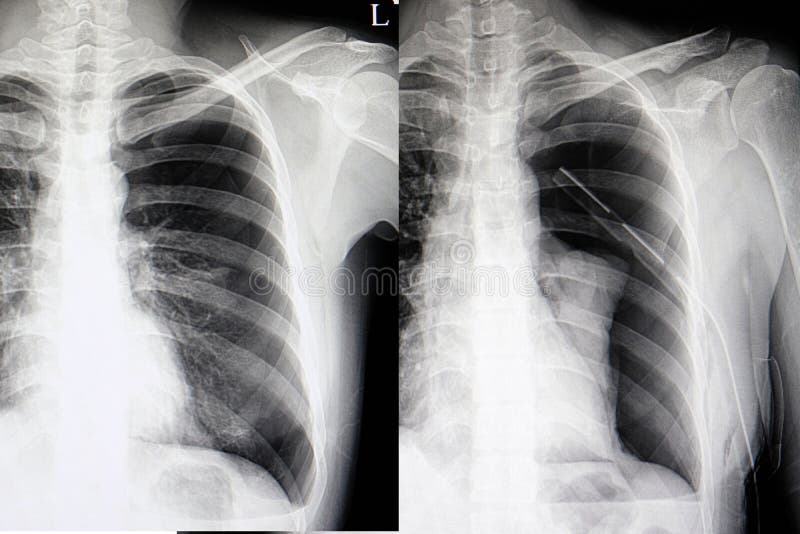

由于情况不妙,王男被紧急送往医院抢救。经医生诊断,确认他患上自发性气胸,其右肺因胸膜腔内积气过多受压,体积已缩至正常大小的三分之一。

医学资料显示,气胸是指空气进入胸膜腔造成积压的状态。自发性气胸尤其青睐特定群体,包括体态偏向瘦高的年轻男性、长期吸烟者,以及本身患有肺部基础疾病的人士。